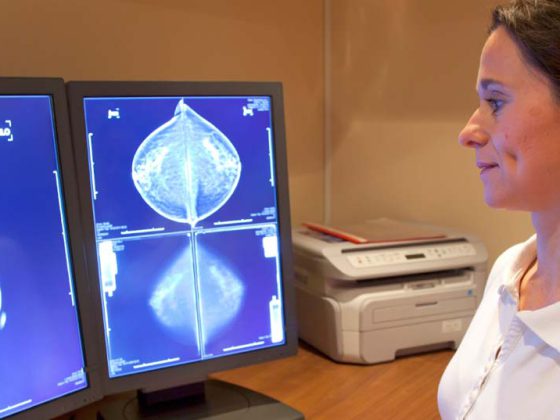

Gemäss neuen Daten erhöht passives und aktives Rauchen das Brustkrebsrisiko deutlich. Besonders gefährdet sind junge Frauen nach der Menarche und vor der ersten voll ausgetragenen Schwangerschaft (FFTP). Ausserdem scheint für Lungenkrebs vor allem die erste Zigarette am Morgen ausschlaggebend zu sein.